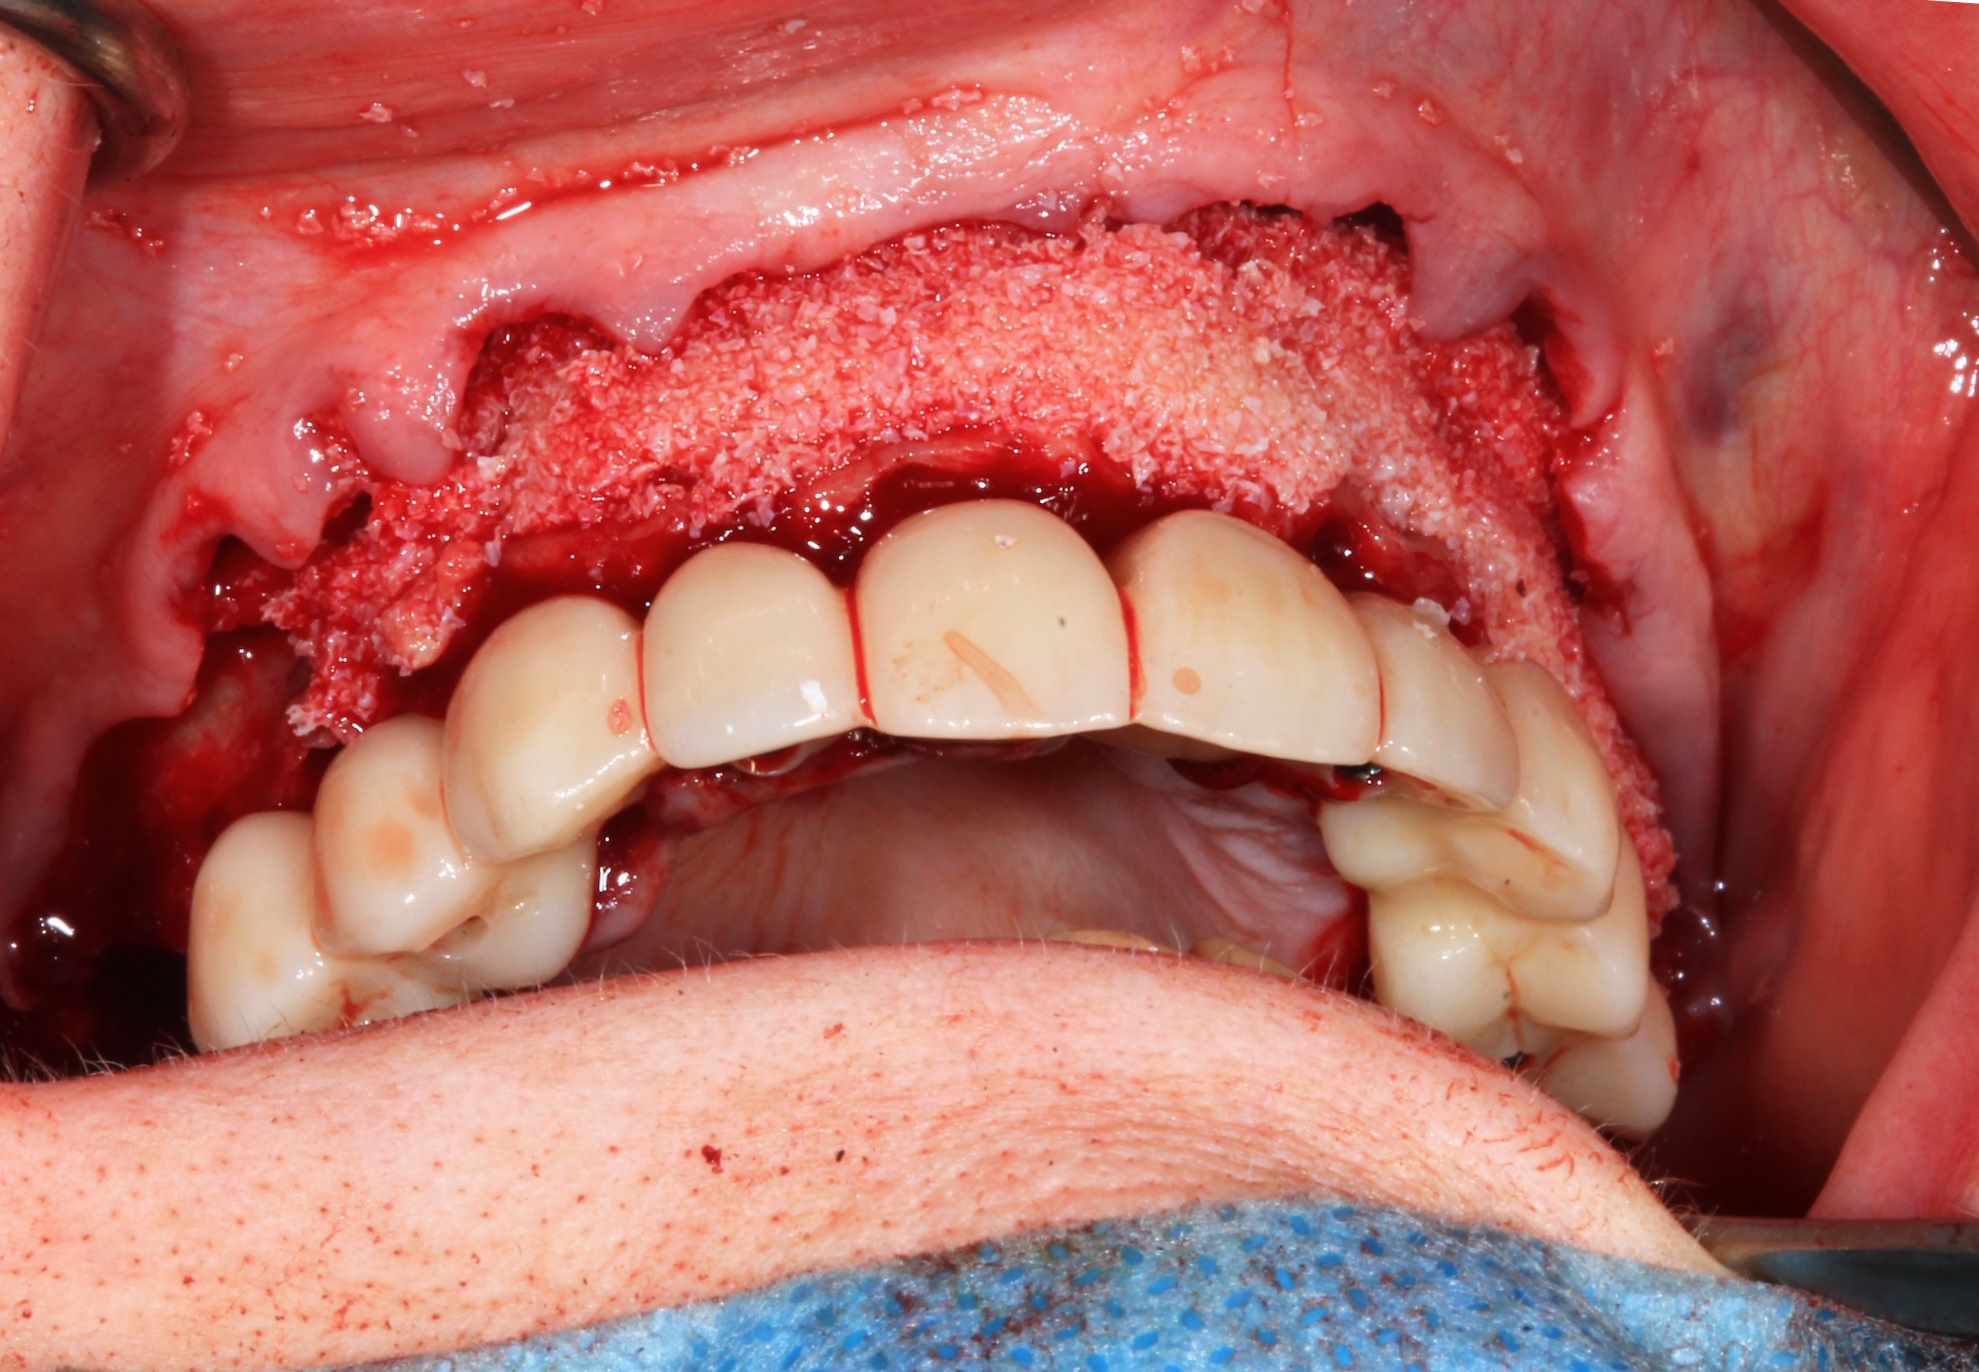

Fixation du guide de forage sur le guide clavette. pose des implants, des piliers ( tres classique ), et du bridge zircone rosenscrew. Stickybone The Graft, sutures suspendues et résultat post op et un mois.